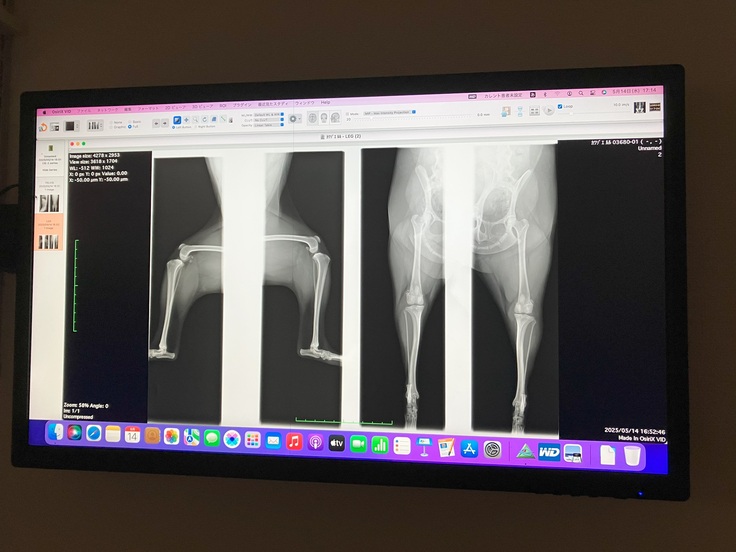

先生から別の病院で詳しく検査したほうがいいと言われたため、後日別の病院で検査したところ、両膝ともパテラ(グレード2~3の中間)と診断されました。

検査時のレントゲン1

検査時のレントゲン2

脛骨粗面転移術と滑車溝形成術という手術を行うとのことです。